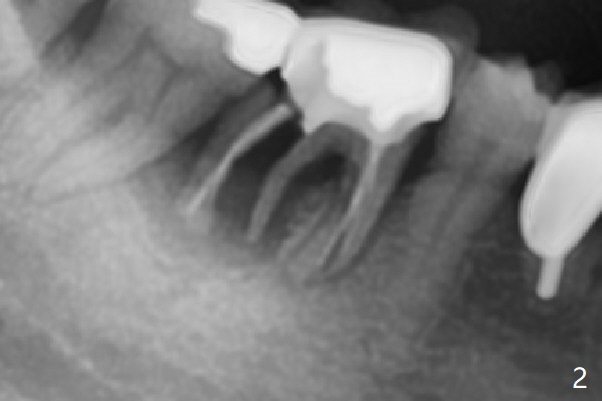

A 66-year-old woman loses a lot of bone at #30 in 4-5 months (Fig.1,2). There is severe buccal swelling, suggesting loss of the buccal plate and easy collapse of the gingiva after bone graft. In addition to an immediate provisional, periodontal dressing will be applied for support and seal. To prevent abutment screw loosening, guide will be used for implant placement in the most ideal trajectory (Fig.4). A tissue-level implant will provide with more security in prevention of screw loosening (Fig.5). If immediate implant is impossible, bone graft will be placed. Four months later, retake 5x5 cm CT for lab to determine the fitness of the guide.